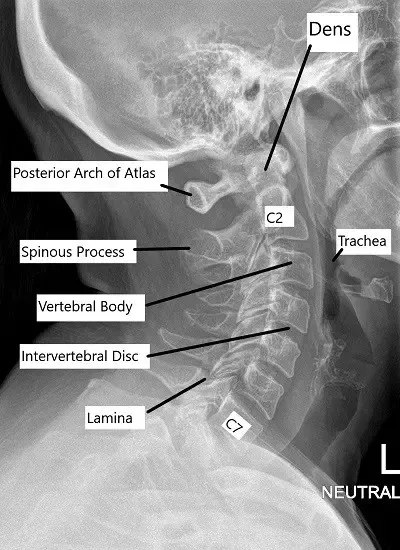

- Columna cervical (cuello): 7 vértebras (C1-C7)

La columna cervical comienza en la base del cráneo y termina en la parte superior del tórax. La columna cervical ayuda en el movimiento de la cabeza al tiempo que proporciona estabilidad. La columna torácica conecta la columna cervical con la columna lumbar, empezando en la parte superior del pecho y terminando en la parte media de la espalda.

Las radiografías proporcionan una visualización básica de la alineación de la columna vertebral y la integridad ósea. Los TAC ofrecen imágenes detalladas de las estructuras óseas y son útiles en traumatismos o afecciones degenerativas. La RM es la mejor herramienta de diagnóstico por imagen para evaluar los tejidos blandos, incluidos los discos intervertebrales, los ligamentos, las raíces nerviosas y la médula espinal.